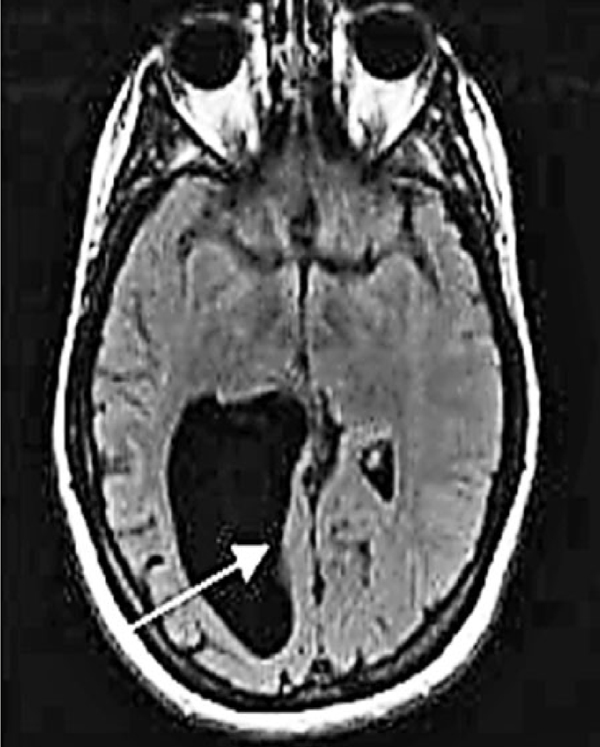

美婦大腦驚現檸檬空洞

■空洞

美國34歲女子科恩自小不能辨認數字、搞不清方向、有社交障礙,多年來被誤診為學習障礙及過度活躍症,直至2007年接受磁力共振掃描,醫生方發現她右腦內有個檸檬大小的空洞,意味她天生缺少判斷空間及數理的頂葉組織,幸好之後遇上專家協助,現時生活已不需再事事依賴他人。

科恩出版回憶錄《Head Case: My Brain And Other Wonders》,講述以往不知病因時對自己的問題非常憤怒,試過自摑,甚至有自殺傾向。神經脊椎按摩師解釋,這情況是因頂葉被脊椎液沖走,理論上仍然存在,只不過已經萎縮,只要訓練右腦活動,便可逐步建立正常人生。 ■《紐約郵報》